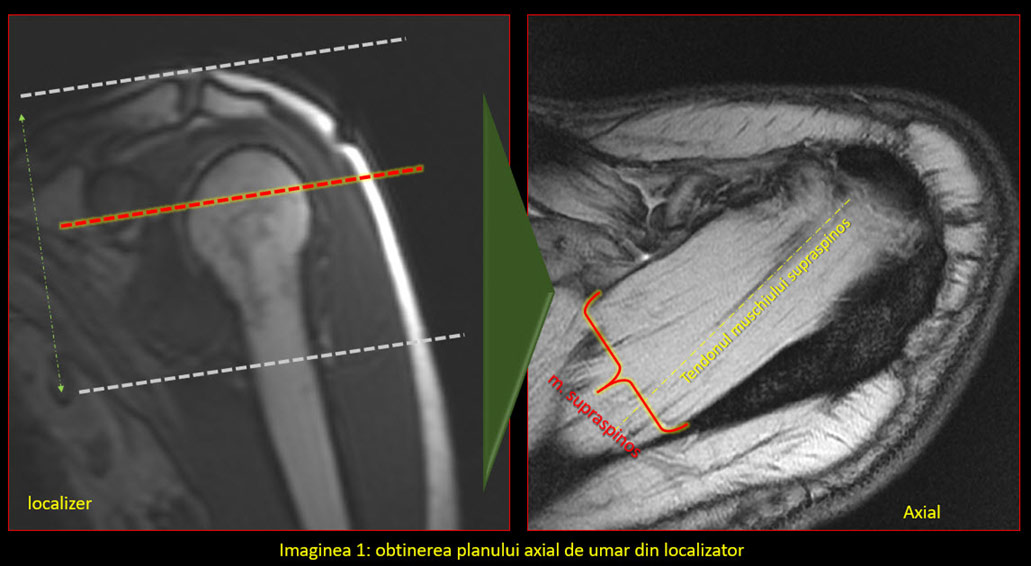

În mod normal, planurile uzual utilizate în imagistică sunt coronal, sagital și axial. În cazul umărului și majorității articulațiilor, oasele și articulațiile au o orientare specială, astfel încât se folosesc planuri modificate. Singurul plan standard este cel axial, deși poate suferi și el modificări în anumite condiții.

Utilizarea planurilor în mod corect permite evidențierea unei structuri, cum ar fi un tendon, într-o singură imagine/secțiune, fără să interfere așa numitul efect de volum parțial (adică să avem într-o imagine părți de anatomie din imaginea următoare sau precedentă). Efectul de volum parțial nu poate fi eliminat în totalitate, dar este cu atât mai mic cu cât secțiunea este mai subțire, spațiul dintre secțiuni mai mic și planul corect aliniat la anatomie.

Astfel:

• Paralel cu tendonul capului lung al bicepsului

• Perpendicular pe marginea anterioară a glenei scapulei

• Paralel/ perpendicular pe difiza humerală

• Paralele față de articulația acromio-claviculară.